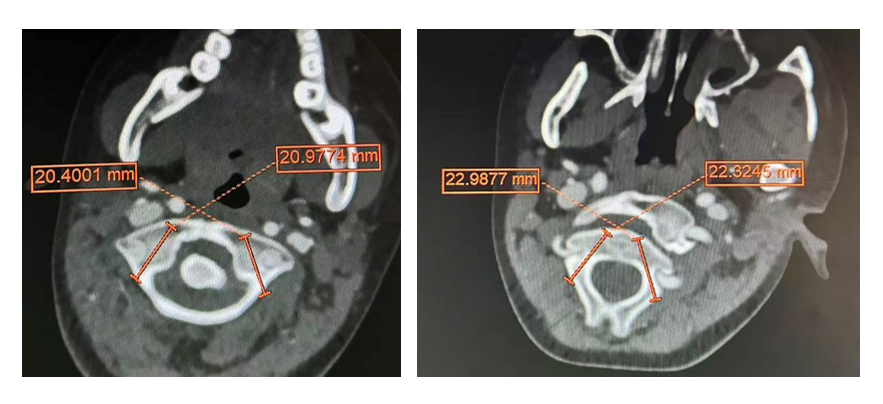

面对挑战,许正伟主任团队在西安市红会医院脊柱病医院院长闫亮、学科带头人贺宝荣主任带领下,为康康制定了周密的个性化方案。术前,三维椎动脉CTA精准“测绘”出脱位的详情与椎动脉的走向。由于患儿无法配合常规牵引,团队决定在术中实施高难度的颅骨牵引复位。

手术日,在麻醉与神经电生理监测团队的全程护航下,主刀医生许正伟主任首先巧妙利用颅骨牵引,为完全脱位的关节实现了初步松解与部分复位。随后,在高端术中导航系统(S8)的实时引导下,将椎弓根螺钉精准、安全地置入寰椎与枢椎的微小椎弓根内。利用螺钉提供的稳固杠杆,脱位的关节被轻柔而坚定地“推”回了正常解剖位置,实现了完美复位。最后,取自患儿自身的髂骨块被植入后方,为永久性骨融合打下基础。